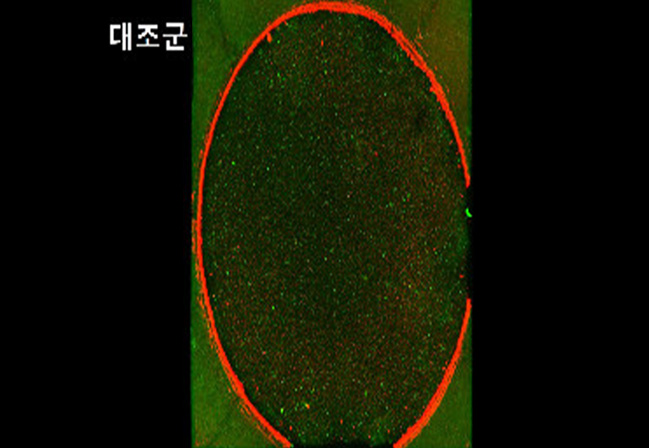

DNA 재생인자 주입술

DNA 재생주사를 통해 필러 시술 후 생길 수 있는 붓기나

미세 염증에 항염 작용을 통해 회복을 빠르게 도와줄

수 있습니다.

DNA 재생인자 미처리 된 인공피부

DNA 재생인자 주입 된 인공피부

음경 피부 회복

항염 작용

세포 재생 촉진